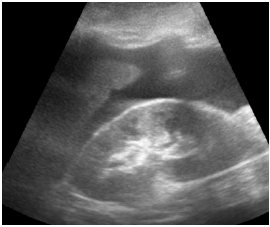

Um paciente de 40 anos de idade, vítima de queda de 9 metros (estava trabalhando quando o telhado cedeu), trazido à sala vermelha pelo SAMU, foi admitido com PA = 80 mmHg x 40 mmHg, FC = 120 bpm e tempo de enchimento capilar = 4 segundos. O emergencista procedeu ao e-fast, que evidenciou o achado apresentado na imagem.

A melhor conduta do emergencista nesse momento é